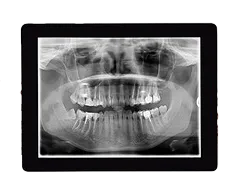

Digital X-Rays

Digital X-rays are one of the most important tools we use to protect and care for your child’s smile. They give us highly detailed images of teeth, gums, and jaw growth—helping us spot issues that may not be visible during a regular exam.

The benefits of our digital X-ray system include:

- Lower Radiation Exposure – Up to 90% less radiation than traditional film X-rays.

- Instant Results – Images appear on-screen within seconds, making it easier to explain findings and next steps to parents.

- Greater Comfort – Smaller, child-friendly sensors mean a quicker, more comfortable process for kids.

- Eco-Friendly – No chemicals or film processing, making it a safer choice for both patients and the environment.

Our gentle, kid-focused approach means we take the time to explain the process in age-appropriate terms, helping children feel relaxed and involved in their own care.